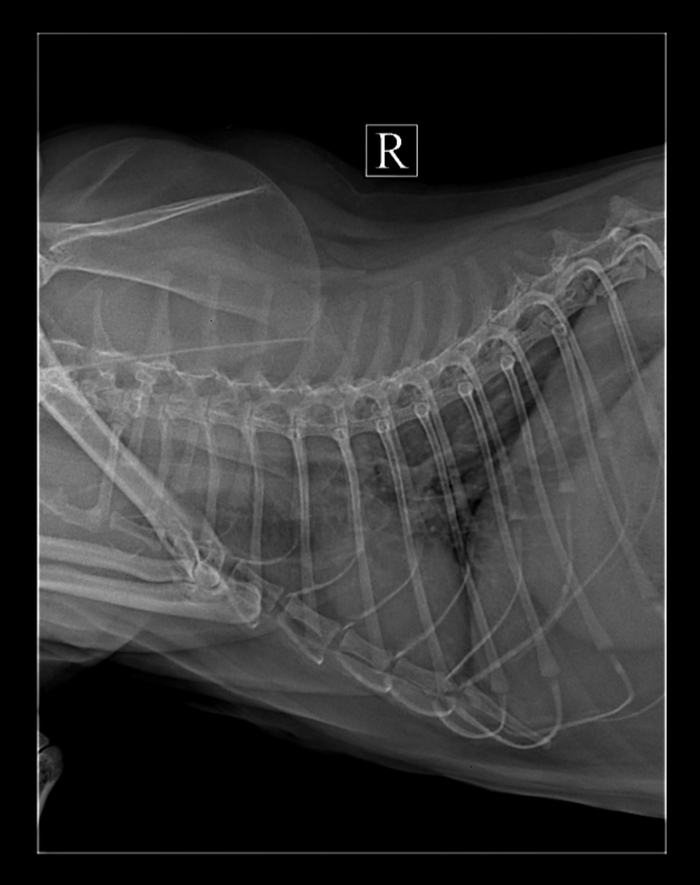

Были сегодня у врача,сделали рентген,сдали кровь.

Лёгкие нормальные но есть небольшое затемнение.

По крови есть инфекция, выписали таблетки,будем принимать 10-14 дней, затем повторный анализ крови.

Если это не поможет,будем сдавать анализ слизистой носа,гортани,6000 с копейками стоит,и если там найдут вирус то ,там что-то с астмой связано,от сложности разное лечение.